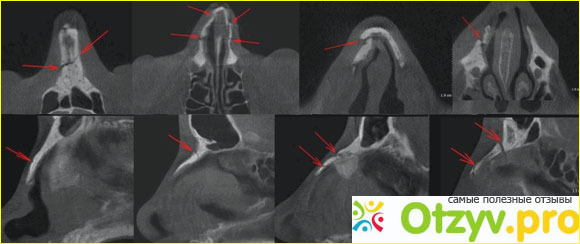

Так вот моя история произошла еще в детстве, и я до конца не могу вспомнить, что я ощущал на тот момент, когда меня доставили каретой скорой помощи. Детство было очень красочным и мы с друзьями часто бесились на улице, к тому же детская площадка у нас и до сих пор оборудована различными качелями, и вот на них мы тогда и решили покататься. И вот с одним очень плотным по весу другом мы решили покататься на качеле-вертелке и вот в один неудачный момент меня развернуло в воздухе и я очень неудобно приземлился на землю, в конечном итоге у меня сместился нос, были очень неприятные как я помню ощущения и потекли слезы с глаз, я помчался домой и когда это зрелище увидела моя мама, когда еще и кровь хлестала из носа, она недолго думая позвонила в скорую помощь, где мне предложили пока не поздно, пока все еще не сраслось, исправить данную ситуацию и мы вместе с мамой поехали в близ распложенную больницу, там я помню эту девушку Анастасию Сергеевну. Помню как она со мной нежно и ласково разговаривала, но то какую боль я тогда испытал, это даже тяжело в словах описать, в конечном итоге они очень сильно повздорили с моей мамой из-за халатного поведения пластического хирурга. Не знаю, каким образом сначала я ей понравился, а потом она начала просто ужасно проводить свою операцию. Во-первых, как мне мама рассказала недавно, ей все же позволили находится рядом во время операции, но уровень санитарии оставлял желать лучшего. Везде все разбросано, и мне грязными инструментами производили операцию, на что опять же возмущалась моя мама, но донести эту информацию до врачей было не возможно, и поэтому Анастасия Сергеевна просто выпроводила мою маму с кабинета с грубыми словами. Я считаю, что действительно во время операции посторонним вход должен был быть запрещен, но вот такое вот отношение - это не показатель ее положительной работы. Во-вторых, мне я как помню обезбаливающее в небольшом количестве укололи. И уже на половине операции я начал ощущать эту боль, они решили мне анестезию не продлевать, поэтому я орал, как потерпевший, мать начала очень сильно за меня переживать.

Но все же операция прошла, но швы от нее в один момент не выдержали, прямо после того, как меня вытащили с кабинета. Я помню, что потерял от этого сознания, и потерял достаточное количество крови. Больно вспоминать эти моменты, Анастасия Сергеевна наверное боялась за состояние своего маникюра, поэтому продолжать от продолжения операции она категорически отказалась. На помощь пришел другой врач, который в конечном итоге исправил ситуацию за довольно короткий срок, за что ему огромное спасибо. И только тогда я успокоился, но осадок от ее работы остался и по сегодняшний день.